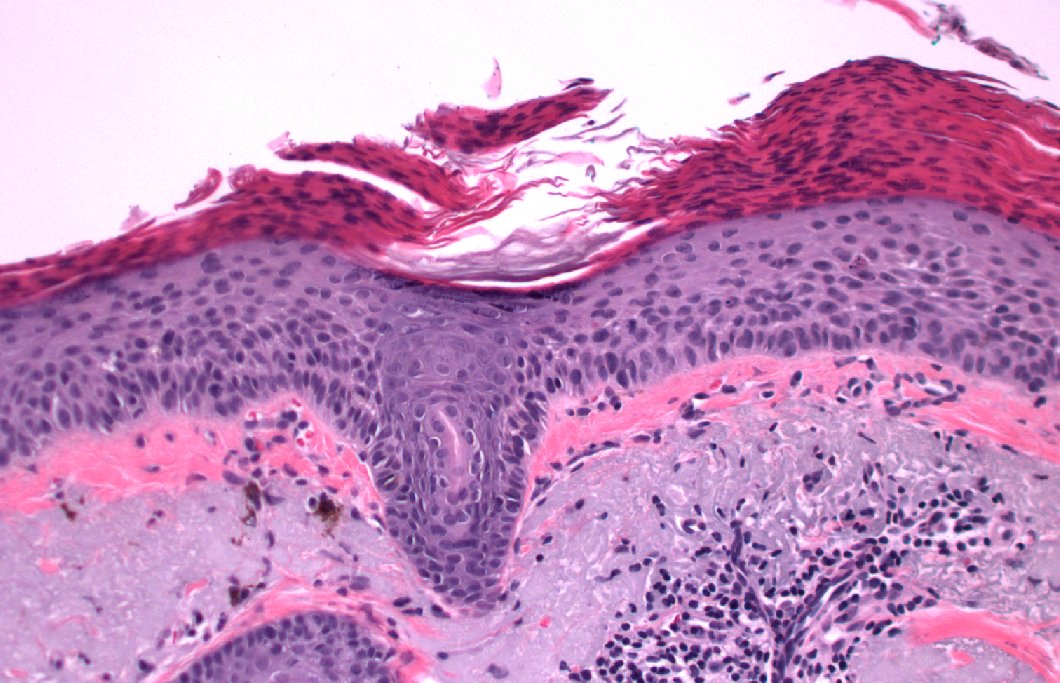

2024 Wk46 ish! RAC9183. M80s Right temple lesion. Previous skin cancers. #TooFarToDiagnose ? #Dermpath